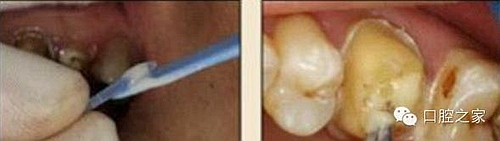

8.根管內(nèi)酸蝕劑的去除

使用全酸蝕粘結(jié)系統(tǒng)粘接纖維樁時,需要應(yīng)用磷酸凝膠對根管進(jìn)行酸蝕處理,然后再徹底沖洗干凈。根管內(nèi)酸蝕劑的殘留是臨床上經(jīng)常發(fā)生且容易被忽視的問題,也是影響纖維樁粘接的重要因素之一。單獨使用三用槍即使反復(fù)沖洗也很難將根管內(nèi)的酸蝕劑清除干凈,尤其是后牙根管。臨床建議應(yīng)用注射器、三用槍和柱狀毛刷,三者聯(lián)合使用反復(fù)沖洗,以免酸蝕劑殘留于根管內(nèi)(圖 19-1至圖 19-4)。有條件者也可使用超聲波蕩洗根管。

圖19-1:冠部及根管全酸蝕。圖19-2:三用槍沖洗。圖19-3:注射器沖洗。 圖19-4:根管毛刷清洗。